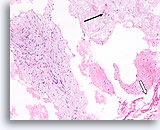

Benigne ductale cellen, Borst FNA, Celblok.

Wat er met ThinPrep® uitzag als een platte laag, ziet er nu uit als een lijn van cellen. U kunt gemakkelijk bij een kleine vergroting zien dat de benigne ductale cellen slechts een dikte van één cel hebben. Let op de licht klevende myoepitheliale cellen aan de buitenkant van de melkgang.

Benigne ductale cellen, Borst FNA, Celblok.

Wat er met ThinPrep® uitzag als een platte laag, ziet er nu uit als een lijn van cellen. U kunt gemakkelijk bij een kleine vergroting zien dat de benigne ductale cellen slechts een dikte van één cel hebben. Let op de licht klevende myoepitheliale cellen aan de buitenkant van de melkgang.

Benigne ductale cellen, Borst FNA, Celblok.

U kunt zien dat de cellen niet echt op elkaar zijn gestapeld weg van het basaalmembraan en de myoepitheliale zone door op te merken dat het cytoplasma aan de rand van het tangentiële gebied (pijl) voorspelbaar overvloediger wordt.

Benigne ductale cellen, Borst FNA, Celblok.

U kunt zien dat de cellen niet echt op elkaar zijn gestapeld weg van het basaalmembraan en de myoepitheliale zone door op te merken dat het cytoplasma aan de rand van het tangentiële gebied (pijl) voorspelbaar overvloediger wordt.